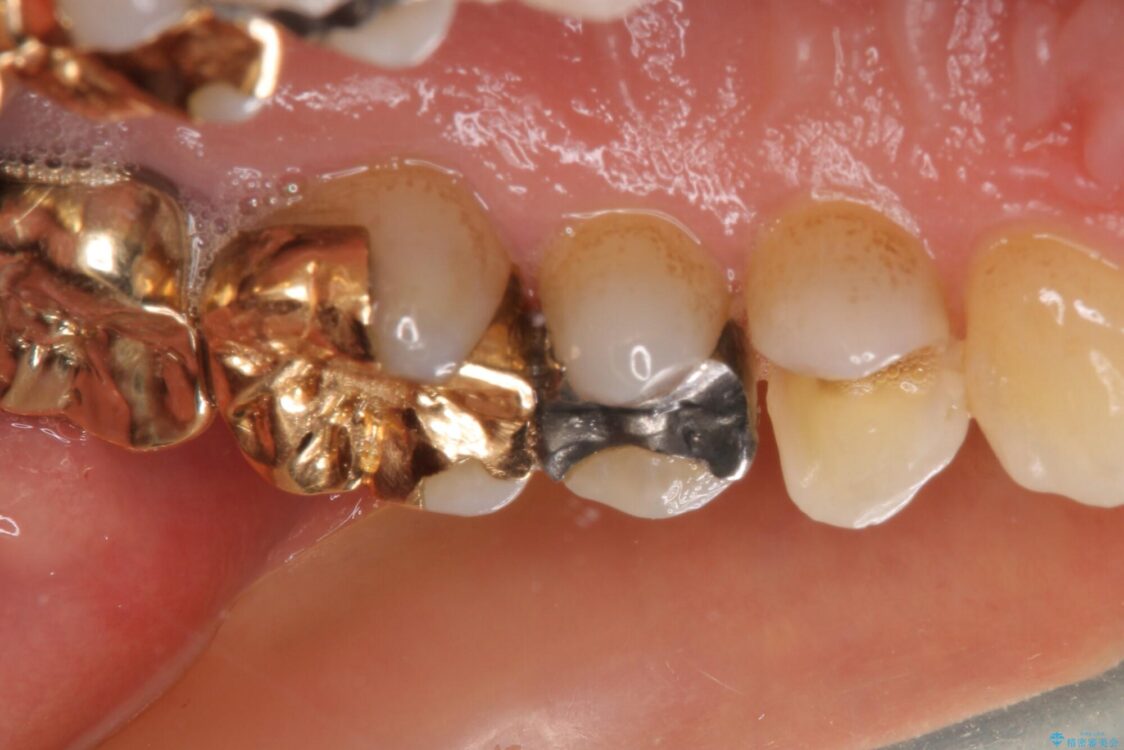

セラミックインレーによる修復治療を実施しました。

正面から見える場所であったため、セラミックインレーで自然な口元にすることができました。

治療後

• 外れてしまった銀歯 セラミックインレーで自然な仕上がりに 治療後画像